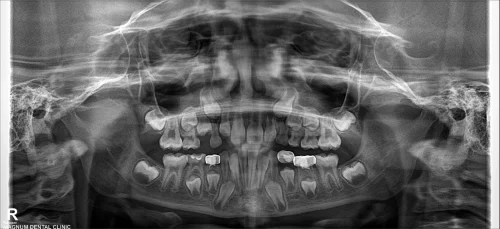

A complete oral examination and an orthopantomogram (OPG) were performed. The extraction socket healed, and the adjacent tooth (#K) received vital pulp therapy and a stainless steel crown. It was necessary to preserve the area of the permanent first premolar (#21).

Without intervention, the loss of space may cause crowding or impaction. The procedure involved applying a unilateral band and loop space maintainer to tooth #K.

The case highlights how a Dubai band and loop space maintainer can prevent space loss for prematurely extracted teeth.

The preventive method that is used by Dr. Pooja ensures a normal eruption of permanent teeth & prevents complicated orthodontic treatments in the future.